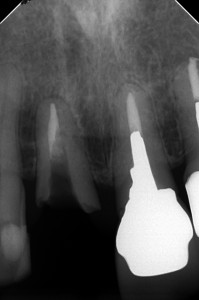

外科的廷出の2か月後

以前、ブログでお話しした歯根破折の外科的廷出の続きです

2枚目の骨とのギャップに注目

たった2か月で、ここまで骨ができるのが凄いですよね( ..)φメモメモ

外科的提出後は意外と骨の回復早いです。

根尖病巣と違うからなんでしょうね。

まだ、すこーし骨縁下欠損がありますが、・・・

術前

術前 術直後

術直後 骨の再生が認められる